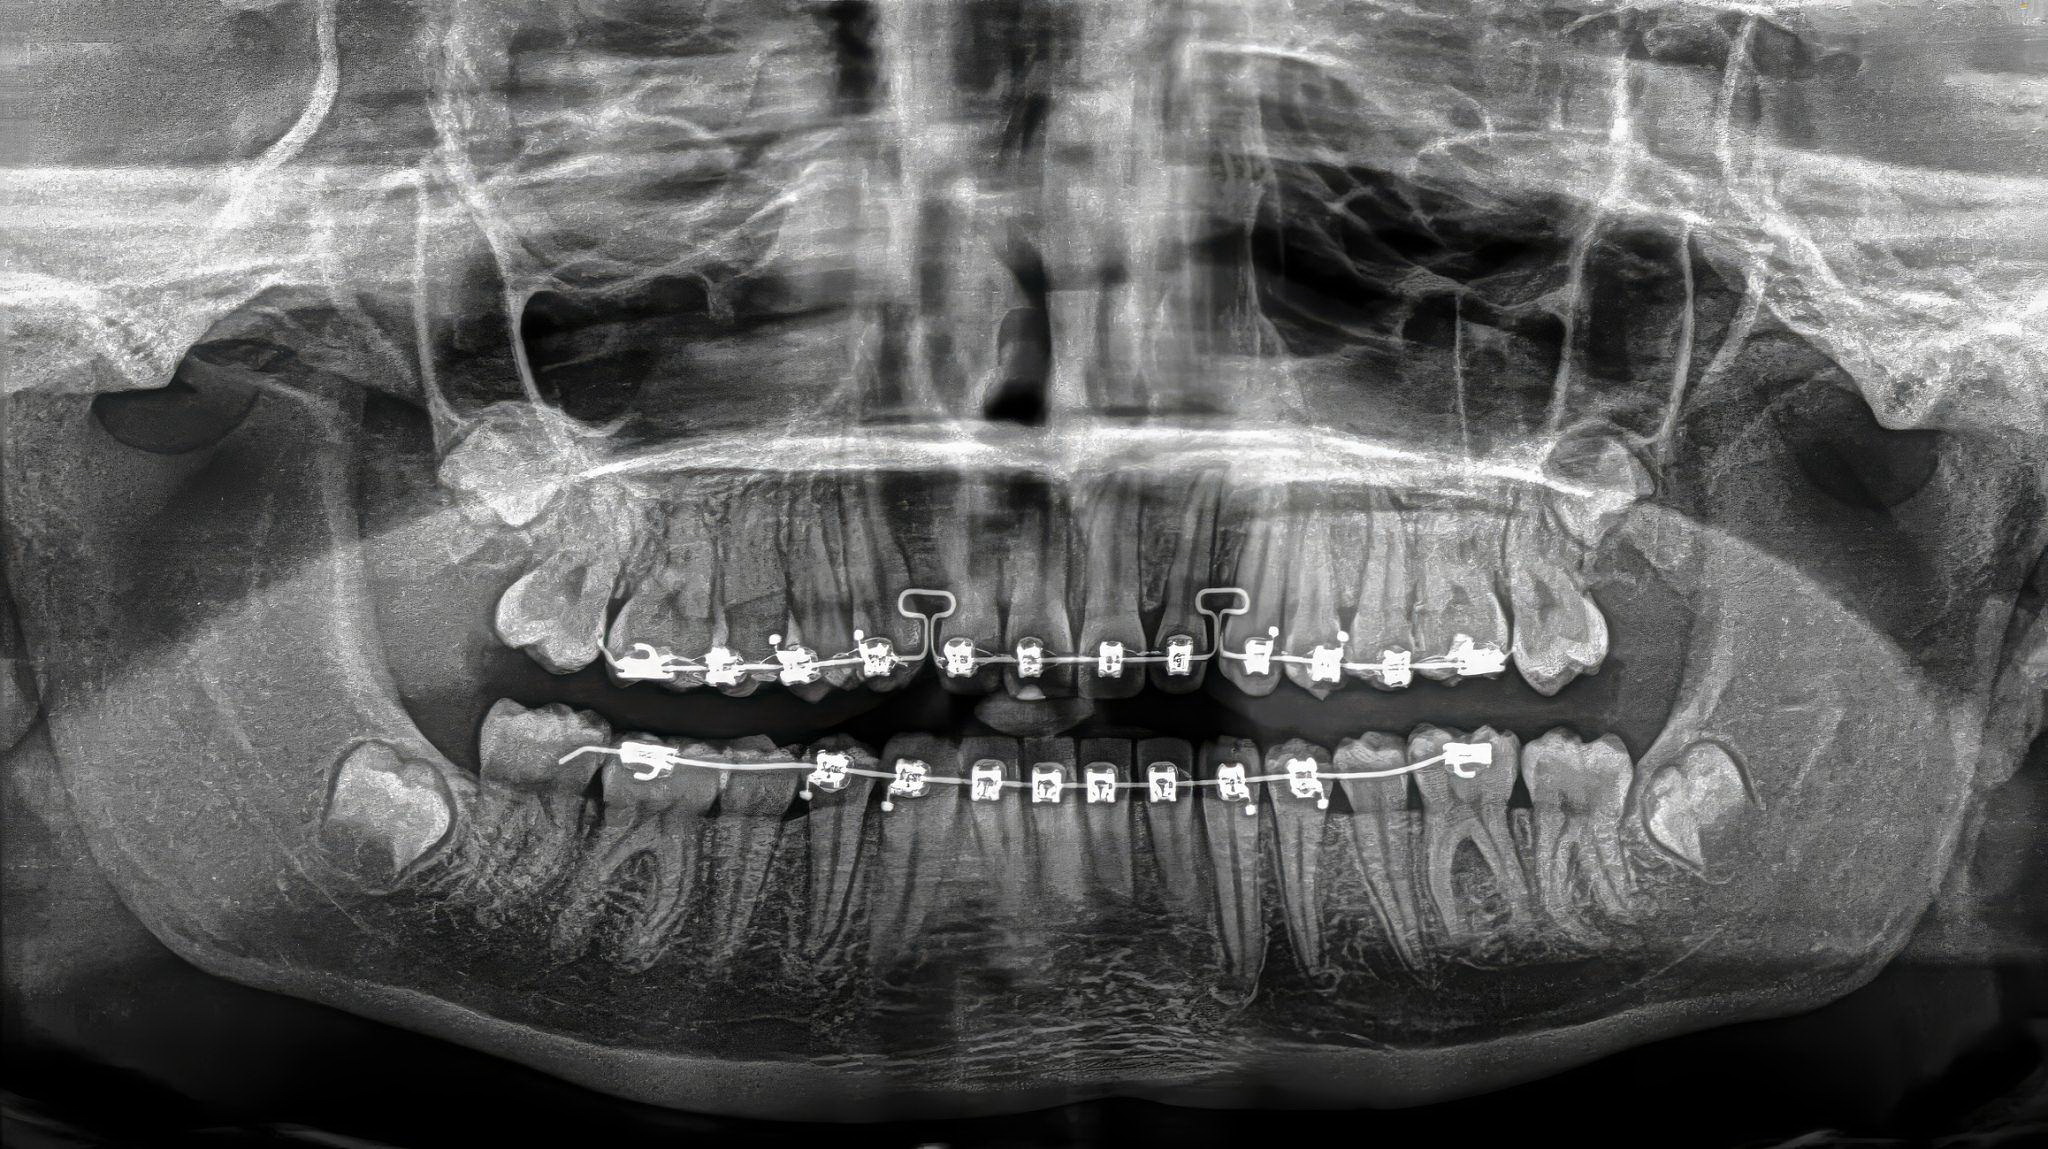

Orthodontic Records & Treatment Planning

Orthodontic success begins with accurate records.

You will gain exposure to:

- Intraoral and extraoral photography

- Radiographic interpretation basics

- Digital scanning and impressions

- Study models and digital workflows

- Case presentation fundamentals

Assistants who understand records improve efficiency and patient case acceptance.